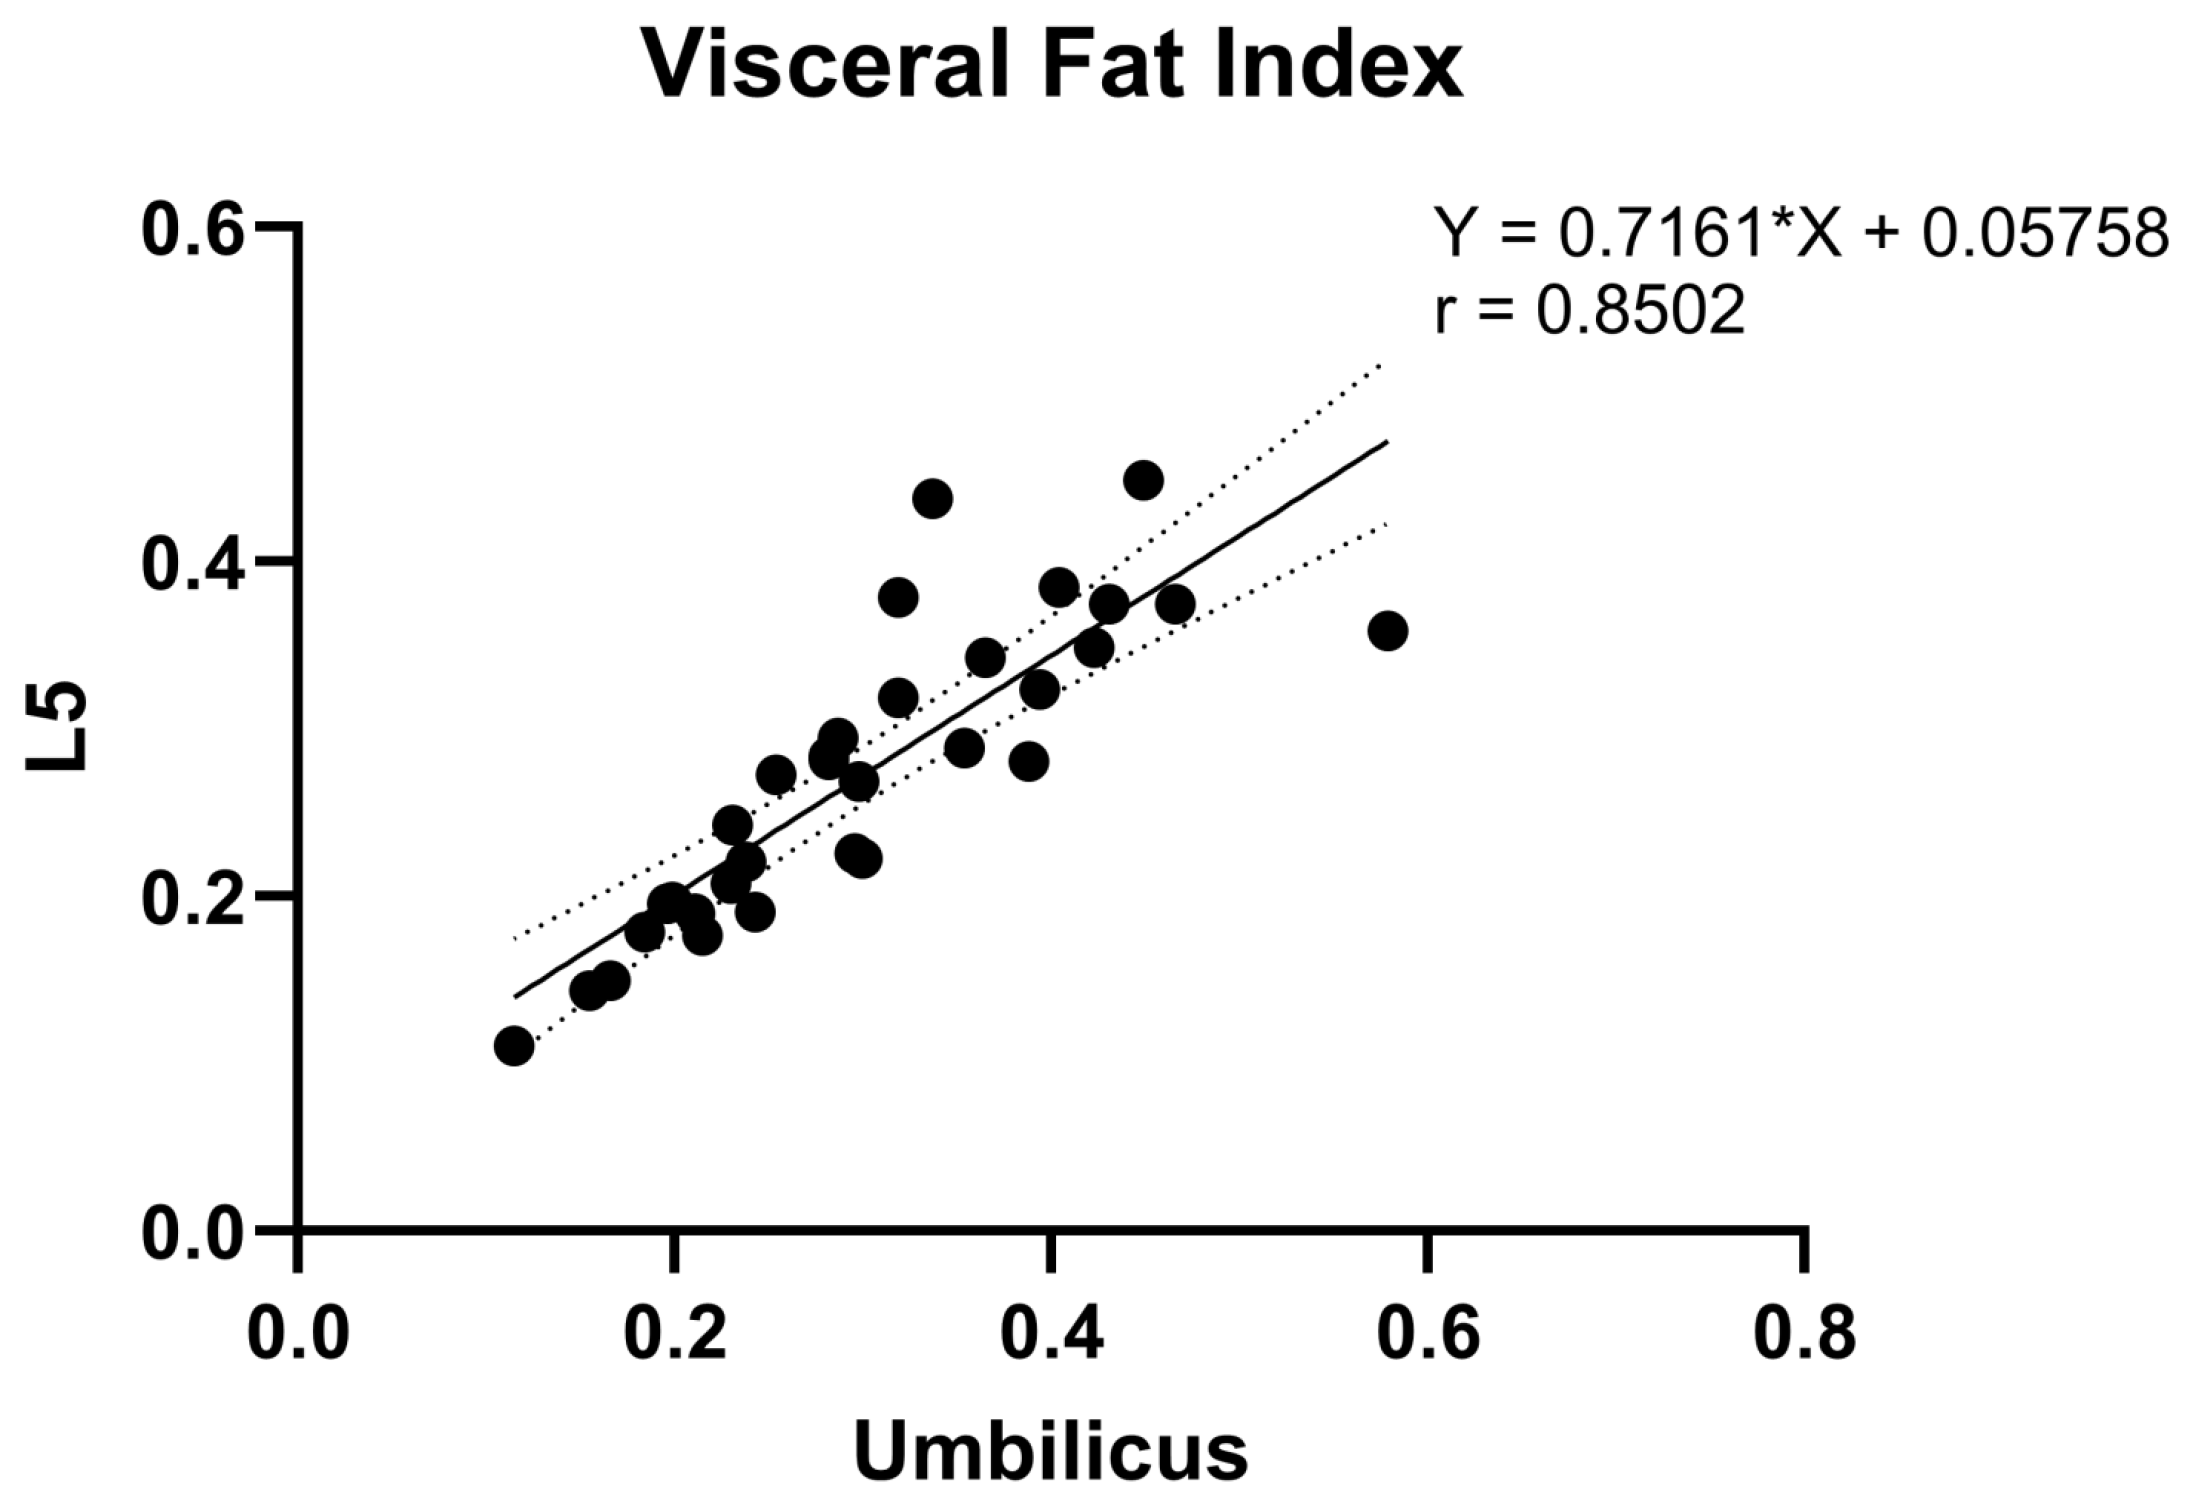

3.3. Correlation Analysis of Fat Measurements between Umbilicus and L5